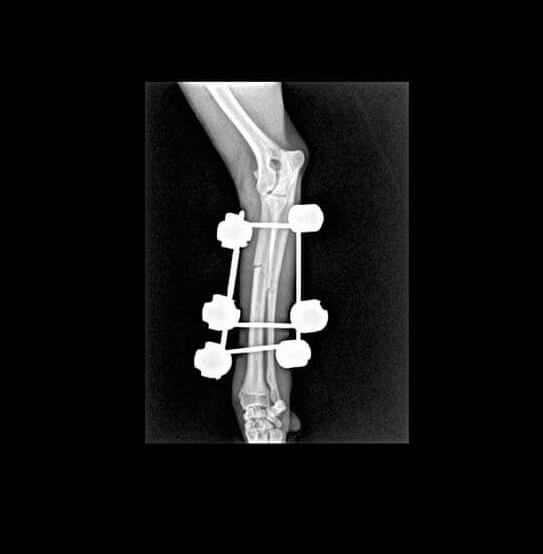

Atès que tot l’examen físic general era normal, li vam realitzar una radiografia. Tal com el propietari s’imaginava, Lluna tenia una fractura a nivell de la diàfisi mitjana del cúbit i el radi (avantbraç).

En aquest cas es va decidir utilitzar uns fixadors externs per donar estabilitat a l’articulació ja que els teixits al voltant de la zona de fractura estaven inflamats i podrien donar problemes de cicatrització si s’hi havia d’incidir per col·locar una placa d’osteosíntesi.

En les següents revisions es va observar molt bona evolució i consolidació òssia de la fractura fins que es va decidir retirar els implants perquè Luna ja pogués fer vida normal.